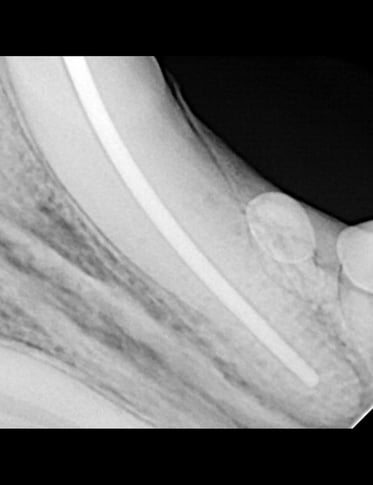

Below: Radiograph of CCF - crown, before RCT and restoration

Upon reaching the pulp chamber, a radiograph was captured to verify cleaning at the designated working length, determined to be 42mm in this case.

Below: Radiograph finding working length